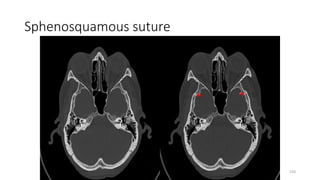

Sphenosquamous suture

SPHENO SQUAMOUS SUTURE